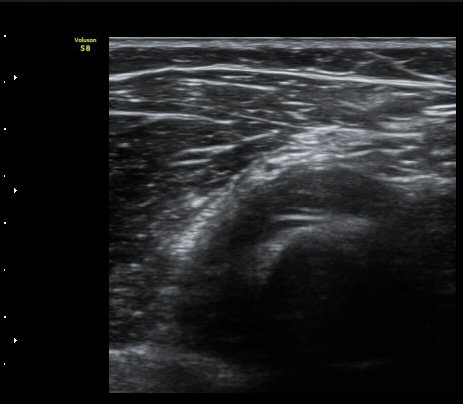

ÃÊÀ½ÆÄ °Ë»ç